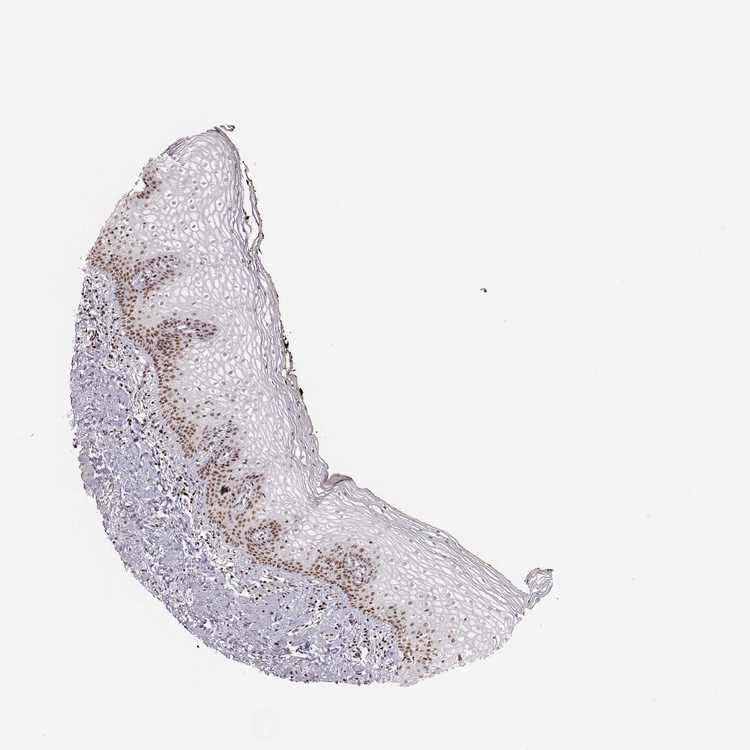

TISSUE PRIMARY DATA VAGINA Show tissue menu

VAGINA - Antibody stainingi

Antibody staining in the annotated cell types in the current human tissue is reported as not detected, low, medium, or high, based on conventional immunohistochemistry profiling in selected tissues. This score is based on the combination of the staining intensity and fraction of stained cells.

Each image is clickable and will lead to virtual microscopy that enables deeper exploration of all samples and also displays staining intensity scores, fraction scores and subcellular localization as well as patient and tissue information for each sample.

Antibody HPA045168Antibody CAB000147Antibody CAB003839Antibody CAB003840Antibody CAB075726Antibody CAB075727

Squamous epithelial cells HighNot detectedNot detectedMediumMediumMedium